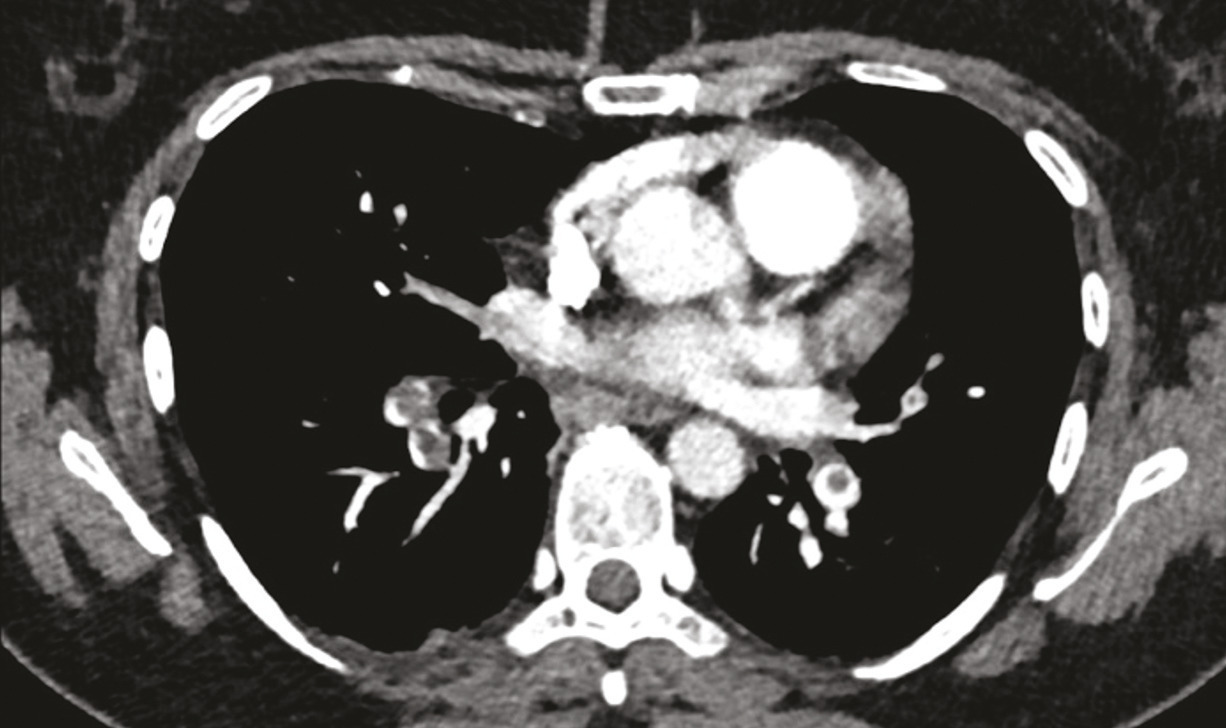

Dans le cas de monsieur M., l’embolie pulmonaire étant probable (en raison de l’antécédent de thrombose veineuse profonde et de la tachycardie à 115 batt/min), l’angio-TDM thoracique est réalisée d’emblée et confirme le diagnostic d’embolie pulmonaire proximale bilatérale (fig. 2) avec dilatation des cavités cardiaques droites et reflux dans la veine cave inférieure.

La prise en charge de l’hyper- tension pulmonaire thrombo- embolique chronique dépend de la localisation des séquelles thromboemboliques, proximale ou distale. Deux examens sont utiles à ce stade, l’angio-TDM thoracique (fig. 6) et l’angiographie pulmonaire (fig. 7).